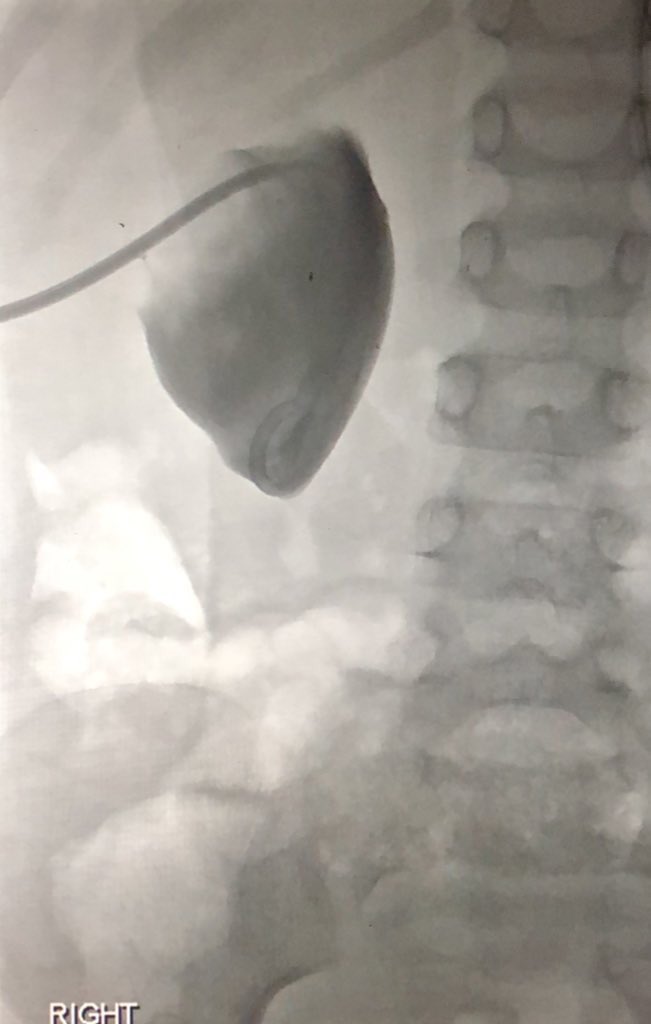

Paediatric nephrostomy

(a short tweetorial)

Technique

•GA

•US guidance for access to PCS

• I I for drain catheter placement

•Seldinger technique with Micropuncture access

–Modified or single exchange

•Trocar (‘single-stick’) technique

2/4